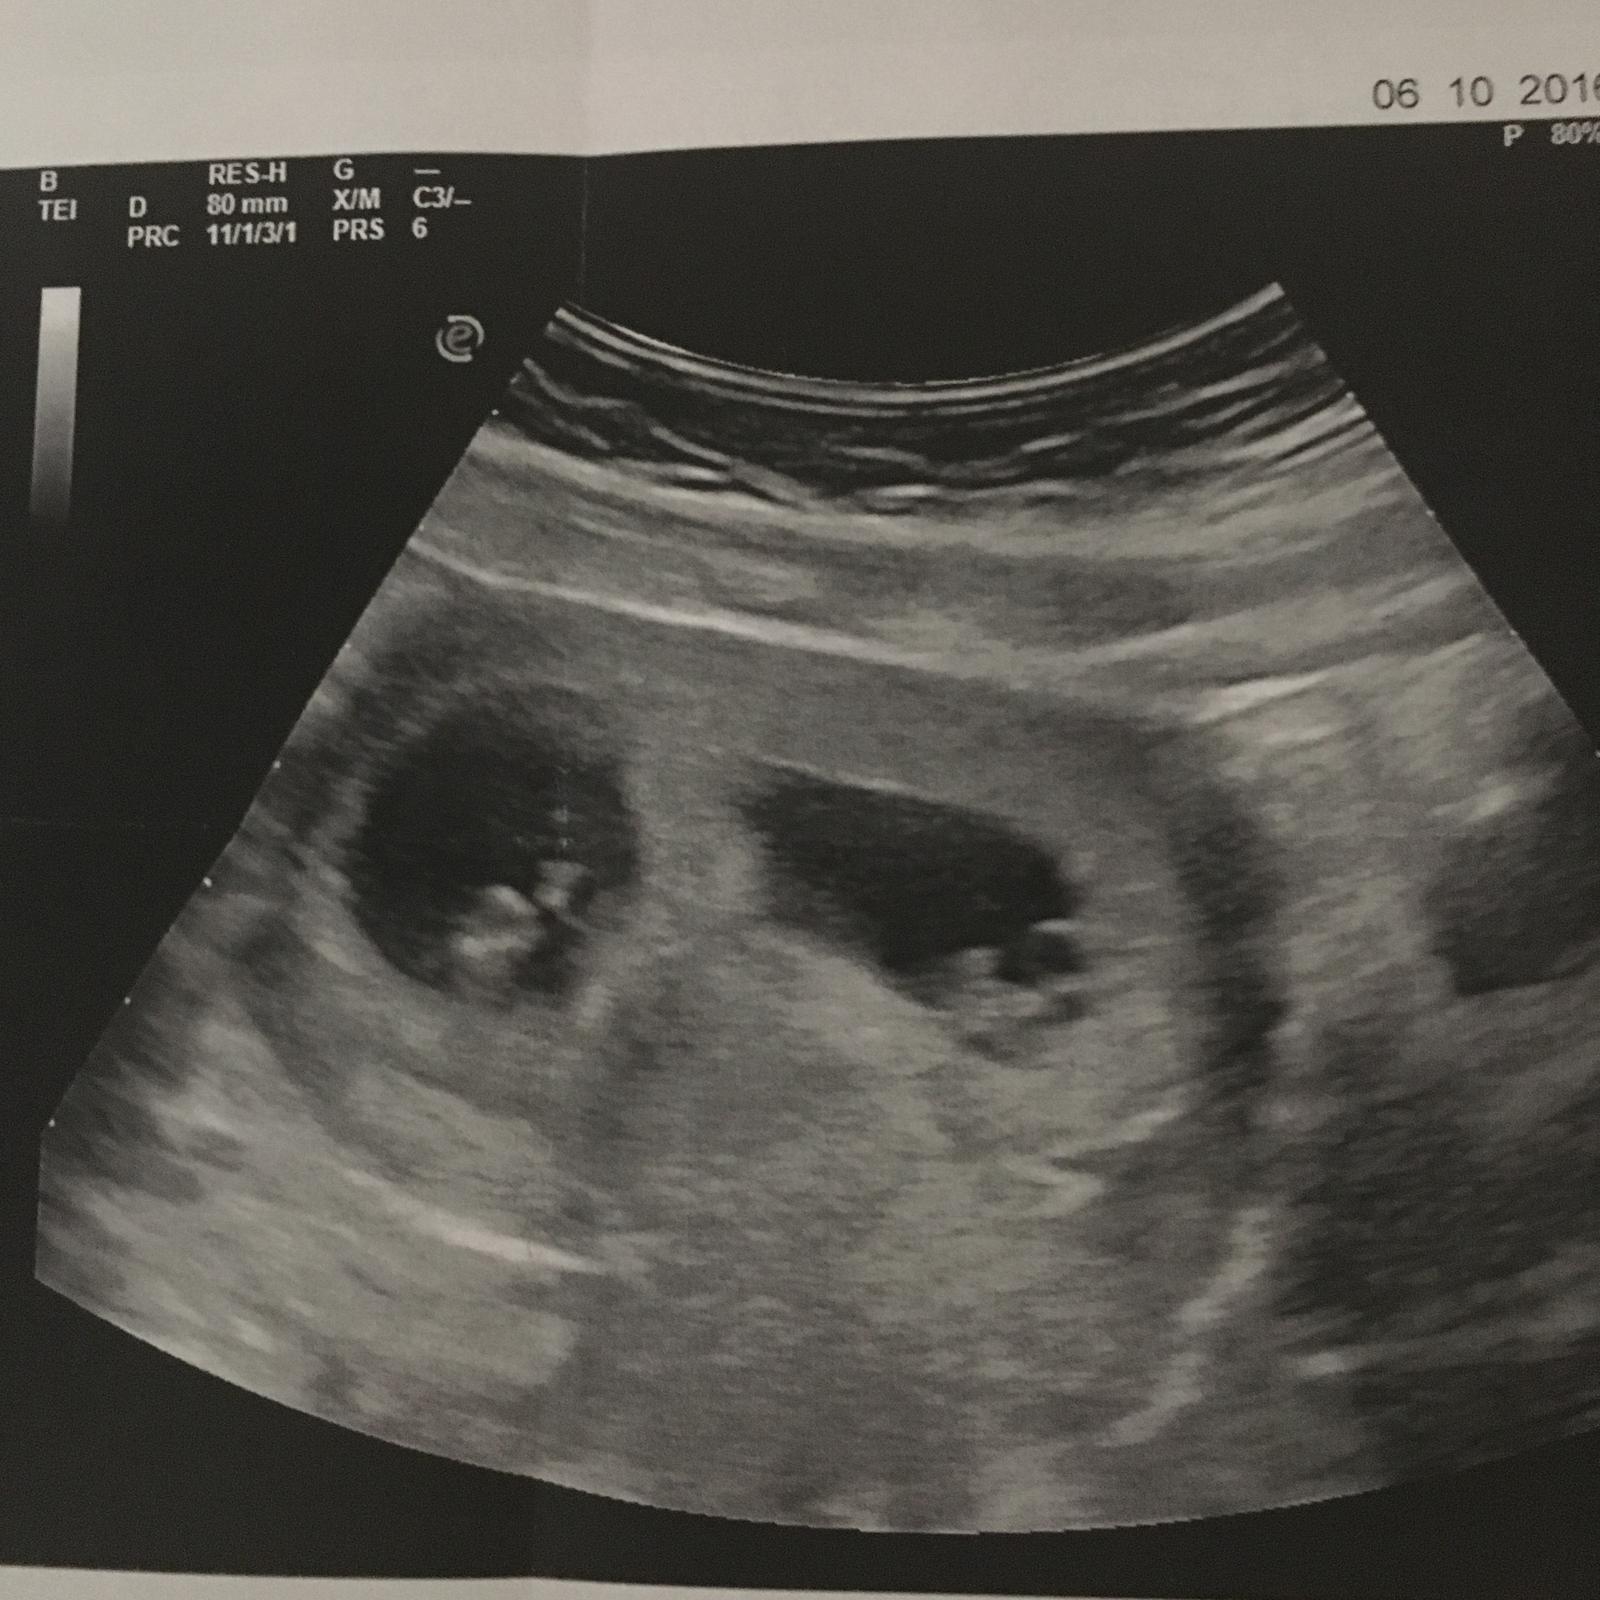

Ahojte tak my sme po dalsom kontrolnom sone. Drobcom biju srdiecka a pekne rastu. Jeden presne zodpoveda 7+3 a druhy je dokonca 7+6. Drzime vam vsetkym :-* :-*